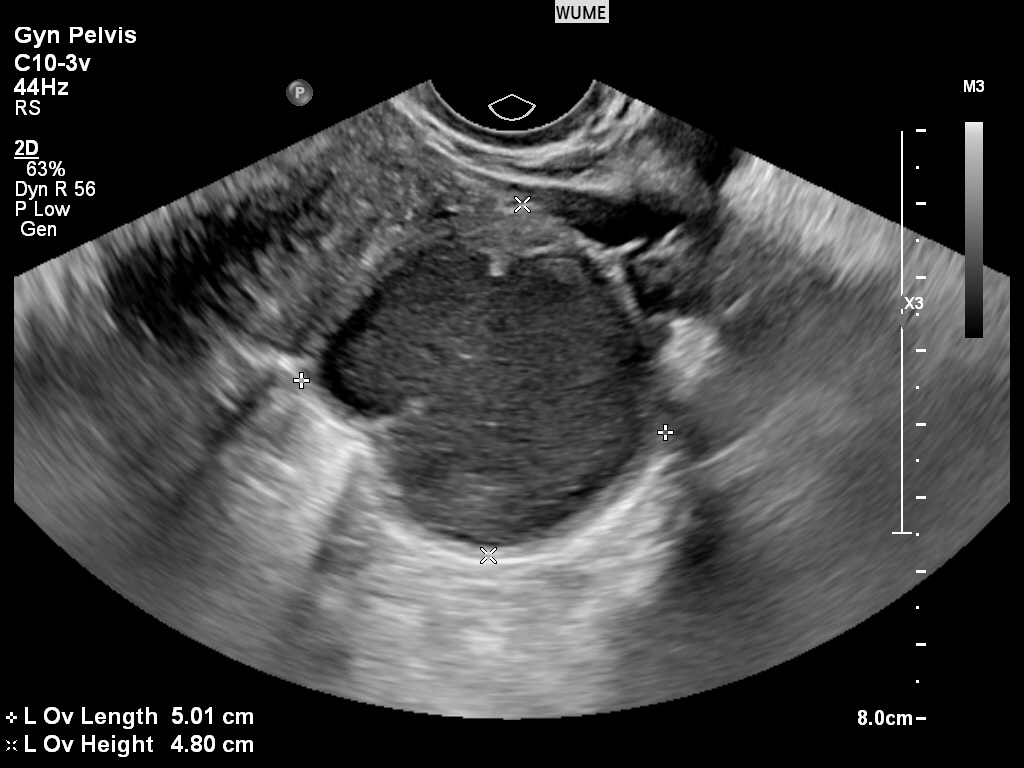

کیست های تخمدان

تخمدان ها اندام های فعالی هستند که به طور طبیعی در طول چرخه قاعدگی "کیست" کوچک ایجاد می کنند. اینها کیست هایی با عملکرد طبیعی تخمدان هستند. این کیست های طبیعی معمولاً به راحتی قابل تشخیص هستند. کیستهای مهمتر را میتوان در طول اسکن تشخیص و ارزیابی کرد و هر یافته مهمی را که در گزارش برای پزشک شرح داده شد و همچنین در زمان سونوگرافی با شما در میان گذاشت.